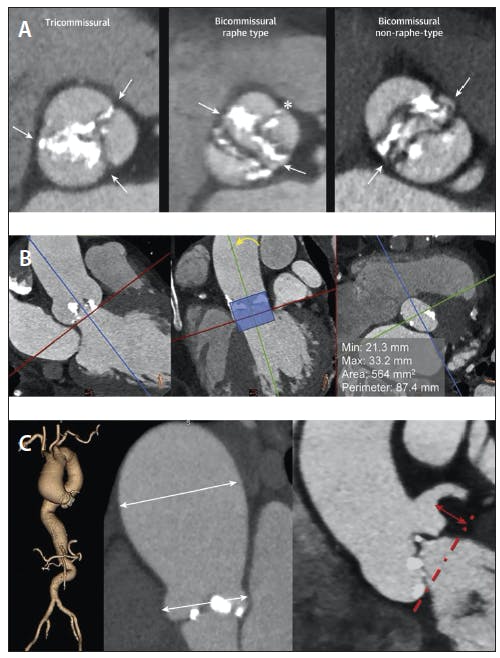

A newer classification based on MDCT imaging has been proposed: tricommissural, where one commissure is completely fused and calcified; bicommissural raphe type, where there is a fused raphe that does not extend the full length of the commissure; and bicommissural nonraphe type, where only two cusps and two commissures are present without any fused raphe (Figure 2A).15 Patients with bicommissural AS were found to have significantly larger intercommissural distances, sinotubular junctions, and ascending aorta dimensions than those with the other subtypes. There were no differences in periprocedural and 30-day outcomes between patients with different BAV morphologies.

Figure 2. Preprocedural planning with MDCT analysis in patients with bicuspid AS undergoing TAVR. Tricommissural type of BAV anatomy is defined by the presence of three commissures (arrows), one of them fused by calcification. Bicommissural raphe type is characterized by two commissures (arrows) and the presence of a raphe that affects the proximal or basal third of the sinus (asterisk). Bicommissural nonraphe type is defined by the presence of two cusps and two commissures (arrows) (A). In bicommissural nonraphe type, define the aortic annulus by orienting a plane crossing the hinge points of the cusps conventionally (left, red line) and a second orthogonal plane (middle, green line) parallel to the device landing zone (middle, shaded zone) (B). The dimensions of the aortic root and ascending aorta, as well as the heights of the coronary ostia relative to the annular plane should also be measured (C). Reprinted with permission from Bax JJ, Delgado V, Hahn RT, et al. Transcatheter aortic valve replacement: role of multimodality imaging in common and complex clinical scenarios. JACC Cardiovasc Imaging. 2020;13(1 pt 1):124-139. doi:10.1016/j.jcmg.2018.10.037

Selection of the appropriate prosthesis size is important to reduce risk of PVR and annular rupture but can be particularly challenging in bicuspid anatomy when there are only two cusps present. An analysis of the BAVARD registry found that there was less oversizing but more frequent underexpansion in patients with BAV as compared to those with tricuspid AS undergoing TAVR with second-generation devices.17 There is debate over the optimal methodology of sizing in BAV patients, with most generally favoring standard annular-based sizing and others using supra-annular sizing at the level of the leaflets or commissures.18 Definition of the aortic annulus in cases of bicommissural nonraphe type should be performed by orienting a plane at the hinge points of the two cusps and intersecting it with a second orthogonal plane parallel to the device landing zone (Figure 2B).19 A recent pilot study used patient-specific computer simulation based on anatomic features extracted from preprocedural MDCT imaging to predict PVR and conduction disturbance with different prosthetic valve sizes and positions. In this small, single-center cohort, these computer simulations led to down-sizing of the valve prosthesis in half the cases, and none had significant PVR after TAVR.20